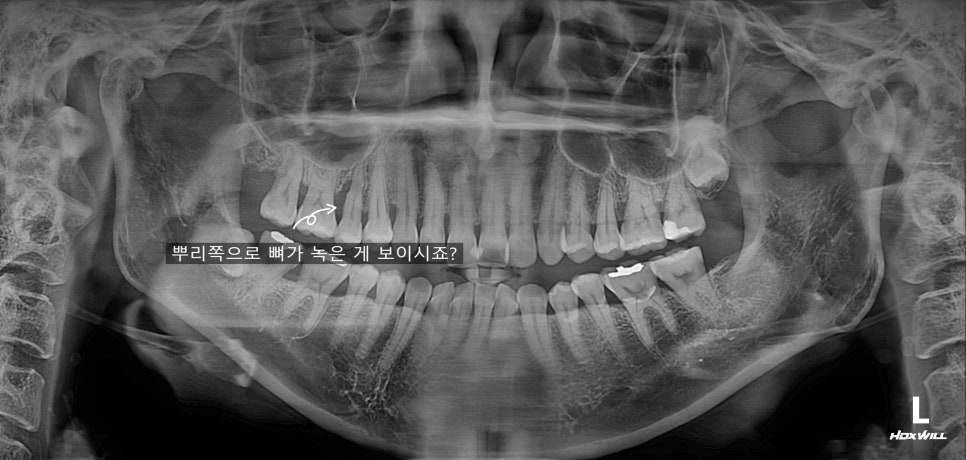

엑스레이에 뼈가 녹은 게 보입니다.

우선 잇몸치료는 해드렸지만

사실상 임플란트가 최선의 치료인 상황입니다.